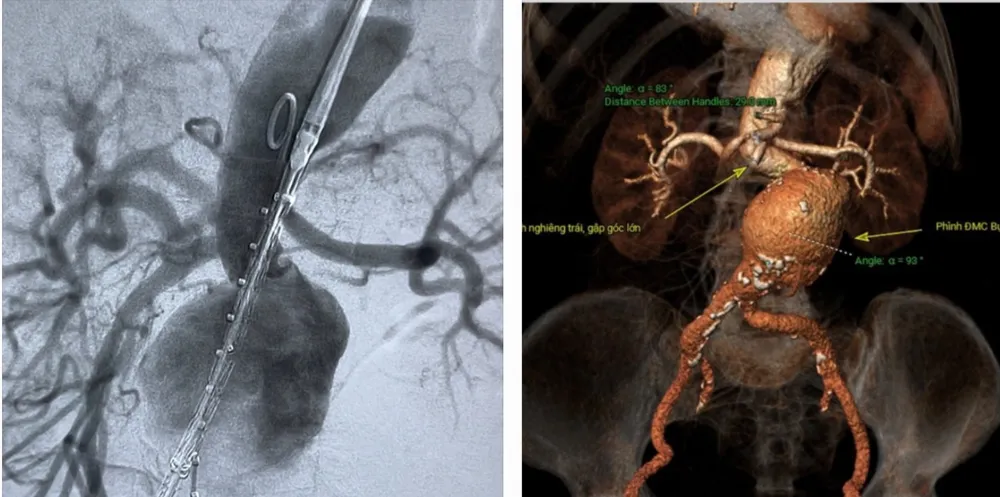

Qua thăm khám và xử trí cấp cứu ban đầu, các bác sĩ chẩn đoán bệnh nhân bị sốc do túi phình lớn động mạch chủ bụng dọa vỡ, nguy cơ vỡ cao. Sau đó, bệnh nhân được siêu âm bụng và chụp CT xác định túi phình rất lớn, động mạch chủ bụng dọa vỡ.

![]() |

Động mạch chủ của bệnh nhân trước khi can thiệp |